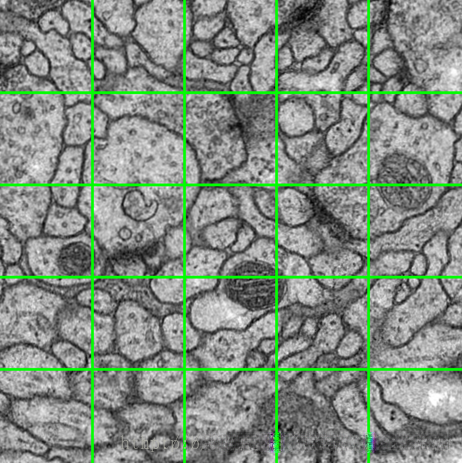

针对任意大小的输入图像的无缝分割的 Overlap-tile 策略。如果我们要预测黄色框内区域(即对黄色的内的细胞进行分割,获取它们的边缘),需要将蓝色框内部分作为输入,如果换色区域在输入图像的边缘的话,那么缺失的数据使用镜像进行补充。